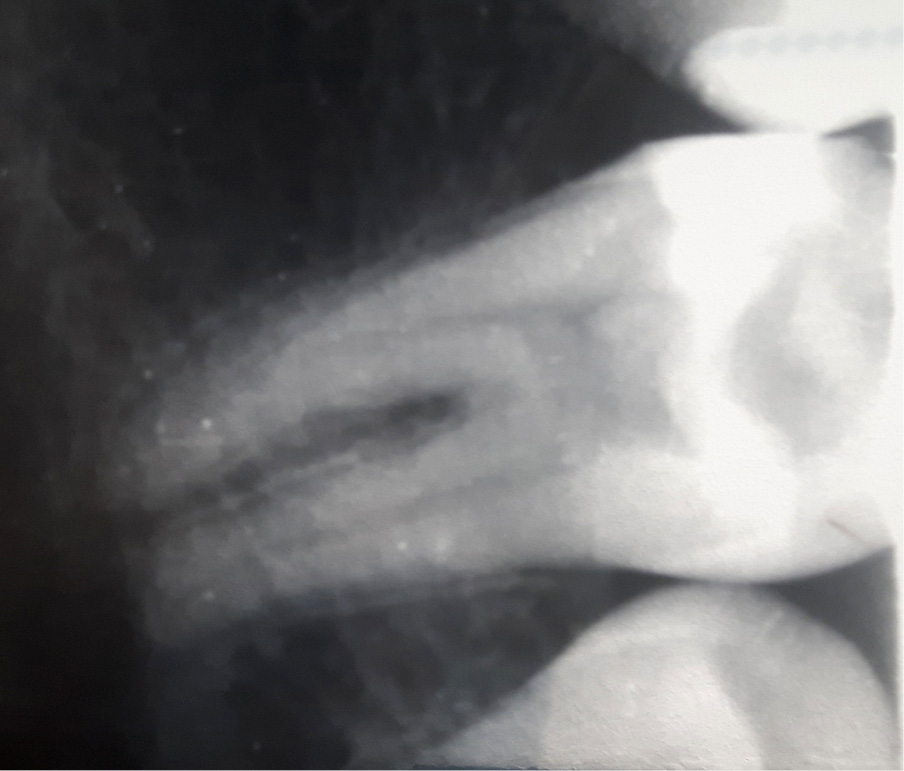

Leczenie endodontyczne zęba 36 u pacjenta z hemofilią typu A

Title: Endodontic treatment of a tooth 36 in a patient with haemophilia type A

Streszczenie: Hemofilia jest chorobą genetycznie uwarunkowaną, recesywnie sprzężoną z chromosomem X. Jest to skaza krwotoczna spowodowana brakiem lub niedoborem jednego z czynników krzepnięcia. W przypadku hemofilii typu A brakuje czynnika VIII [1-2]. Najczęstszymi objawami są trudne do zatamowania krwawienia z uszkodzonych urazem naczyń krwionośnych i wylewy krwi do stawów, mięśni czy narządów wewnętrznych, często pojawiające się samoistnie [1-4]. Chorzy ze skazami krwotocznymi są szczególną grupą pacjentów w gabinecie stomatologicznym. Występuje u nich ryzyko trudnych do zatrzymania krwawień, spowodowanych nawet drobnymi urazami podczas zabiegów stomatologicznych. Dlatego pacjenci obarczeni tym schorzeniem muszą być odpowiednio przygotowani do wizyty w gabinecie dentystycznym, a zabiegi powinny być wykonywane ze szczególną ostrożnością [5-6].

Summary: Haemophilia is a genetically determined disease recessively linked to the X chromosome. It is a haemorrhagic disease caused by a deficiency or complete absence of coagulation factors. In [...]